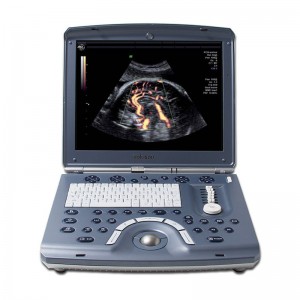

Toshiba Xario™ XG: Všestranný barevný Doppler ultrazvukový systém s vynikající kvalitou obrazu a 3D/4D

Toshiba Xario™ XG je barevný ultrazvukový systém se sdílenými službami Doppler, který kombinuje vynikající kvalitu obrazu s ergonomickým designem. Tento všestranný přístroj je vybaven řadou pokročilých funkcí, které zajišťují konzistentní poskytování vysoce kvalitních snímků v širokém spektru klinických aplikací, včetně břicha, prsou, malých částí, štítné žlázy a specializovaných OB/GYN aplikací s 3D/4D zobrazením.

Xario™ XG se vyznačuje vynikající kvalitou obrazu, která je zobrazena na velkém 19palcovém LCD monitoru. Je vybaven technologií ApliPure™, která lékařům poskytuje ultrazvukové snímky s výjimečnou čistotou a bohatými detaily ve všech zobrazovacích režimech. Díky intuitivnímu ovládání a pokročilým funkcím je Xario™ XG efektivním nástrojem pro každodenní klinickou praxi.